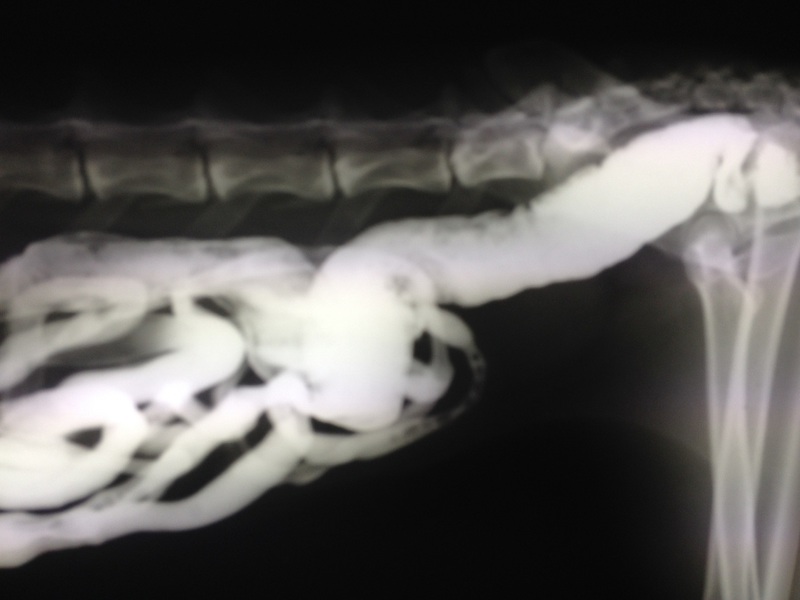

Guten Tag! Ich bin Frida und mir ging es wirklich, wirklich elend. Ich kann Euch sagen, ein Leben begleitet von ewiger Übelkeit mit Erbrechen ist irgendwann kein so schönes Leben mehr. Schliesslich landeten wir bei Doc UU. Der gab mir so weisses Zeugs (Anmerkung Autorin: Kontrastmittel) ein. Na ja, irgendwie hat's nicht so schlecht geschmeckt aber es war halt ganz schön viel. Schliesslich wurde ich geröngt und dank dieses Mittels stellte Doc UU fest, dass mein Darm voller Haare war. Ebenfalls dank dieses Mittels verliessen diese vielen Haare ENDLICH meinen Darm..... jetzt geht es mir wieder gut und die ewige Kotzerei - pardon der Ausdruck - hat Ende. Herzliche Grüsse von Frida